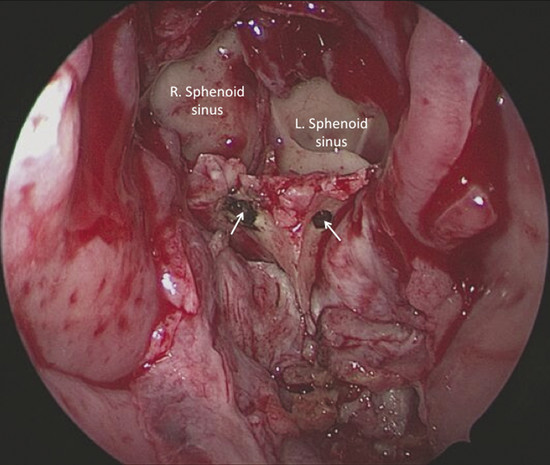

The flap is sutured anteriorly to the edge of the perforation and inferiorly to the mucosa of the floor of the nasal cavity with absorbable stitches. In its most posterior portion, a suture passing through the soft palate is performed. It is anchored to the sphenoid rostrum with two stitches that pass through two holes made in the sphenoid rostrum, above the choana, thus creating a new septum made of two layers of pericranial flap (Fig. 21‑5, Fig. 21‑6, Fig. 21‑7, Fig. 21‑8).